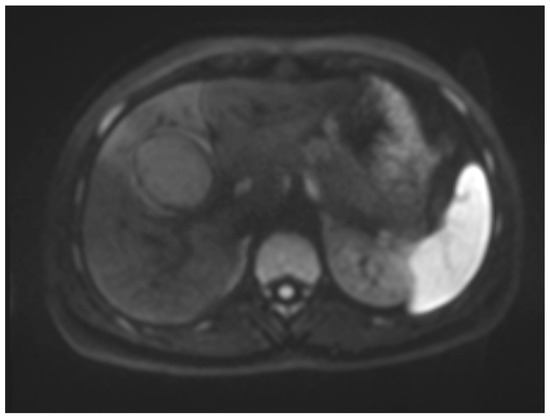

Six months later, a second ultrasound scan and a consecutive MRI scan to follow-up and control the success of the therapy were performed. The ultrasound revealed a decrease in the size of the cyst from 10 cm in maximal diameter to 9 cm and showed multiple circular septations, indicating an involuting cyst (Figure 7). In contrast to the preceding MRI scan, typical T2 hypointense membrane-like structures were observed within the lesion in T2WI. These represented most probably the floating membranes, the typical water-lily sign (Figure 8). T1WI (Figure 9) showed the cyst as a hypointense lesion, but the membranes could only be clearly observed in T2WI. Consecutively, the cyst was classified as WHO-CE3A.

Second MRI scan: Axial T2W MRI scan, where floating membranes forming the water-lily sign after anthelmintic treatment, indicating stage WHO-C3a.

Figure 9.

MR imaging clearly visualizes pericyst, matrix, and daughter cysts. The pericyst appears as a hypointense rim on both T1WI and T2WI due to its fibrous structure and the presence of calcifications. This is a specific feature of hydatid cysts, called the rim sign, mostly better visualized on T2WI [5]. The matrix represents hydatid-fluid-containing membranes of broken daughter vesicles, scolices, and hydatid sand [7]. The hydatid matrix appears hypointense on T1WI and significantly hyperintense on T2WI. However, the limitations of MRI scans are especially observed in stages CE4–CE5, as bigger calcifications are better observed on a CT scan. When daughter cysts are present, they are typically more hypointense than the matrix on T2WI, as observed in our case report [17] (Figure 1). If the membrane is separated, it can shift with movement, resembling a water lily floating on the surface of a pond, previously described as water-lily sign, which was seen in our case report as well [18] (Figure 8).